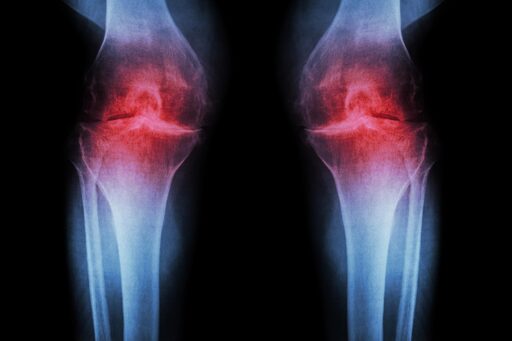

In mice (of course) and human tissue exvivo. Earlier phase 1 studies with 15-PGDH has shown that it is safe and active in healthy volunteers.

Reference: “Inhibition of 15-hydroxy prostaglandin dehydrogenase promotes cartilage regeneration” by Mamta Singla, Yu Xin Wang, Elena Monti, Yudhishtar Bedi, Pranay Agarwal, Shiqi Su, Sara Ancel, Maiko Hermsmeier, Nitya Devisetti, Akshay Pandey, Mohsen Afshar Bakooshli, Adelaida R. Palla, Stuart Goodman, Helen M Blau and Nidhi Bhutani, 27 November 2025, Science. DOI: 10.1126/science.adx6649